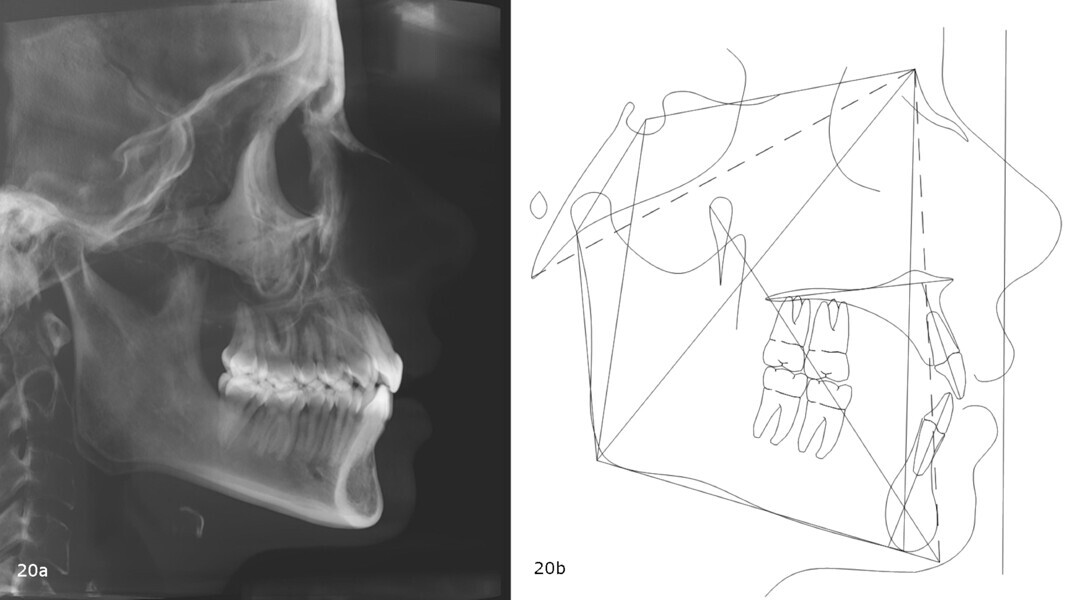

The panoramic radiograph showed prior extraction of all third molars, localised root resorption of several teeth, generally good periodontal health and an atypical condylar morphology, suggestive of temporomandibular joint (TMJ) remodelling or degenerative changes (Fig. 19). The cephalometric radiograph and tracing revealed a mesobrachyfacial skeletal pattern and a tendency towards a Class II skeletal pattern (Fig. 20).

The post-treatment panoramic radiograph showed good root parallelism and no worsening of the pre-existing root resorption or periodontal condition (Fig. 32). The final cephalometric radiograph and tracing showed that, although the patient retained a Class II skeletal pattern, the values had improved owing to mandibular auto-rotation (ANB from 6.9° after splint therapy to 4.4° at the end of treatment). This auto-rotation had also improved the vertical measurements between the end of splint therapy and the end of treatment: maxillary inclination (SN–OP) had decreased from 18.6° to 16.2°, Ricketts’ facial axis from 92.7° to 91.4° and Jarabak’s sum of angles from 392.0° to 387.6° (Fig. 33).